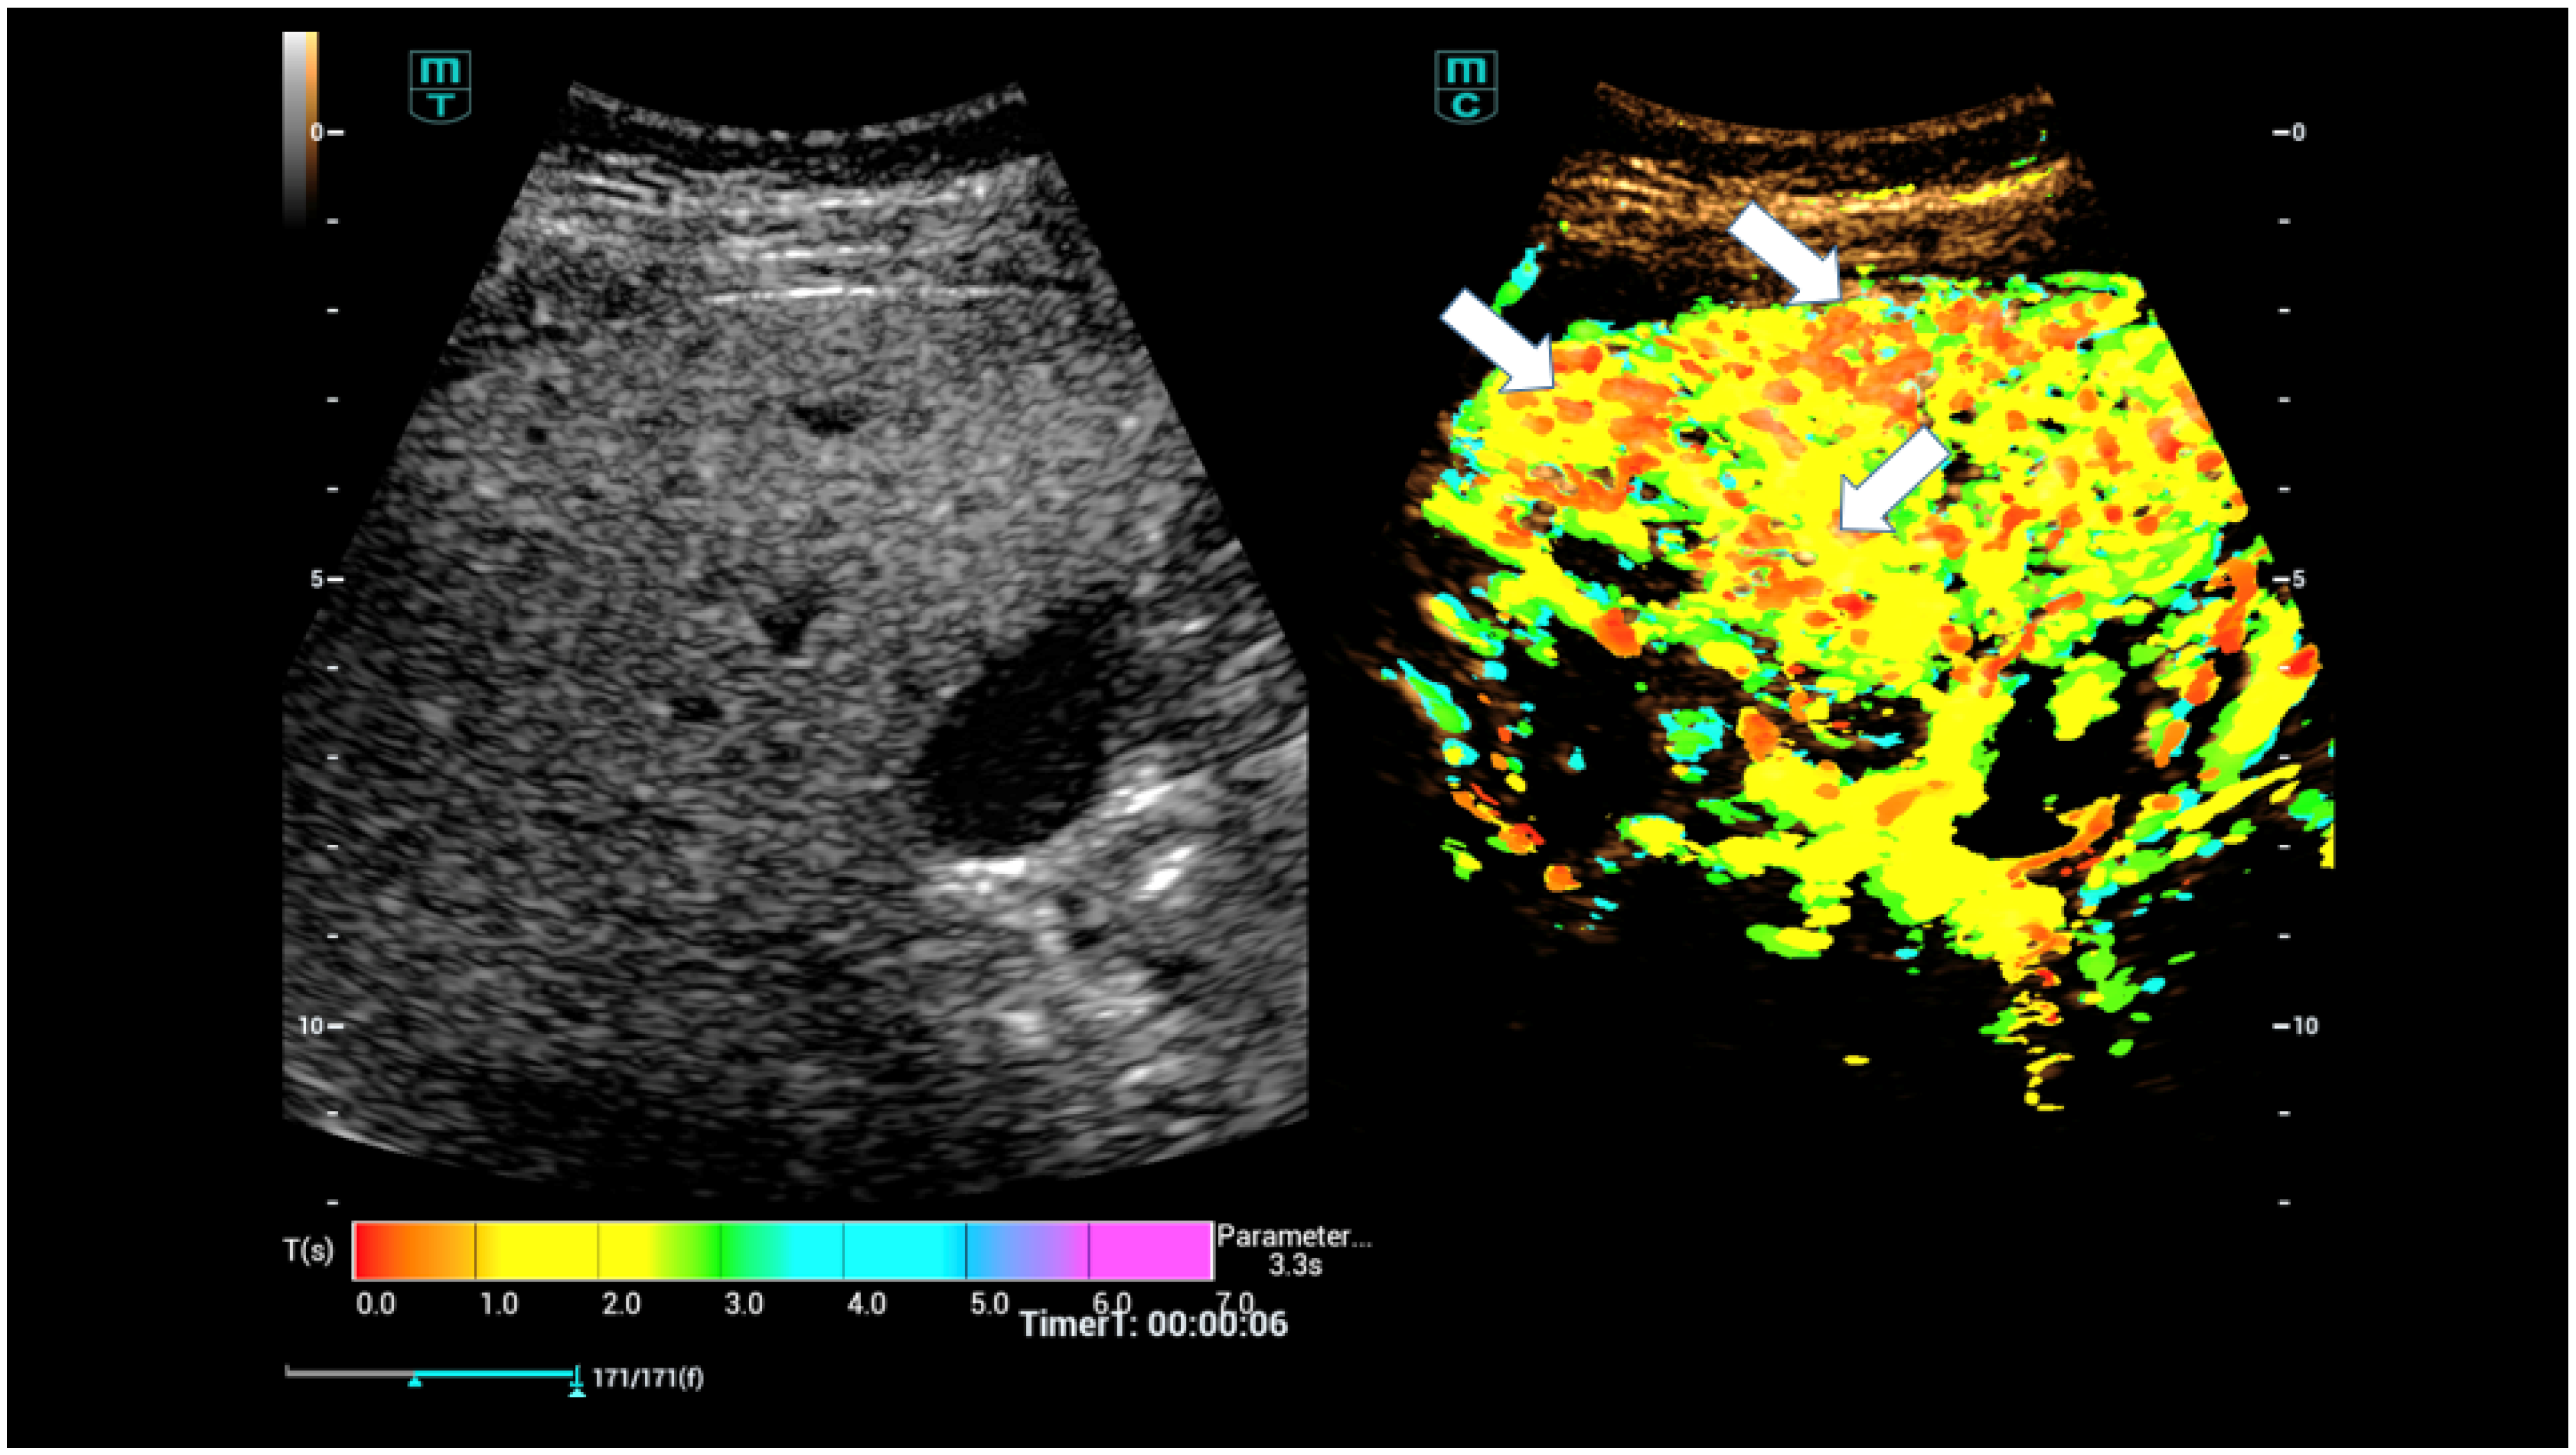

- Dropco, I.; Kaiser, U.; Wagner, L.; Brunner, S.M.; Schlitt, H.J.; Stroszcynski, C.; Jung, F.; Yi, D.; Herr, W.; Jung, E.M. Color Mapping using Ultrasound System-integrated Perfusion Software for Evaluation of Focal Liver Lesions: A Possible First Step for More Independent Reading. J. Gastrointestin. Liver Dis. 2023, 32, 479–486. [Google Scholar] [CrossRef]

- Schelker, R.C.; Andorfer, K.; Putz, F.; Herr, W.; Jung, E.M. Identification of two distinct hereditary hemorrhagic telangiectasia patient subsets with different hepatic perfusion properties by combination of contrast-enhanced ultrasound (CEUS) with perfusion imaging quantification. PLoS ONE 2019, 14, e0215178. [Google Scholar] [CrossRef]

- Schelker, R.C.; Barreiros, A.P.; Hart, C.; Herr, W.; Jung, E.M. Macro- and microcirculation patterns of intrahepatic blood flow changes in patients with hereditary hemorrhagic telangiectasia. World J. Gastroenterol. 2017, 23, 486–495. [Google Scholar] [CrossRef]